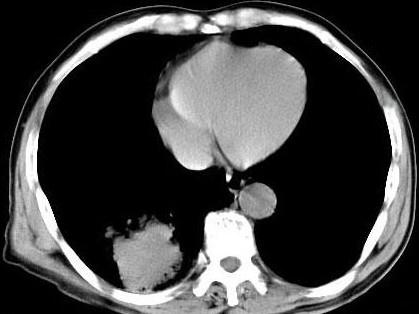

问题 男,66岁,胸痛一月,胸部CT如图,最可能的诊断是 ( )

选项 A、右下肺错构瘤 B、右侧炎性假瘤 C、右下肺动静脉瘘 D、右下肺肉瘤 E、右下肺周围型肺癌

答案 E